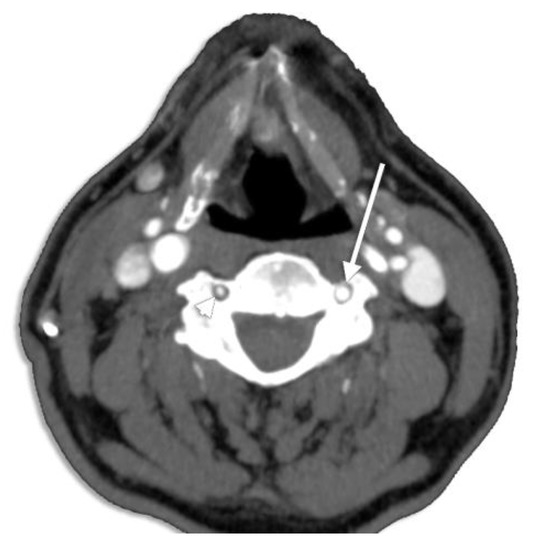

3.5. Prevalence of the VA Course

3.5.1. Tortuosity

3.5.2. Straight V1 Segment Prevalence